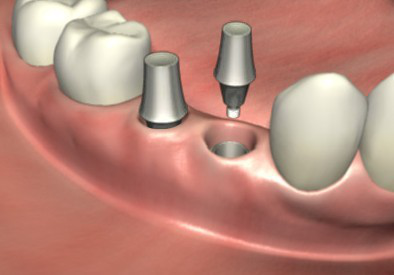

ЁЁЁЁ3ЁЂАВзАгњКЯЛљЬЈЪЙжжжВЬхДЉГібРіИЃЌЕШД§2~3жмШУШэзщжЏГЩаЮЁЃ

ЁЁЁЁ4ЁЂШэзщжЏГЩаЮКѓгУгРОУЛљЬЈЛЛЯТгњКЯЛљЬЈЃЌНЯКѓАВзАЙЬЖЈжжжВбРЙкБуЭъГЩСЫжжжВбРЪжЪѕЁЃ